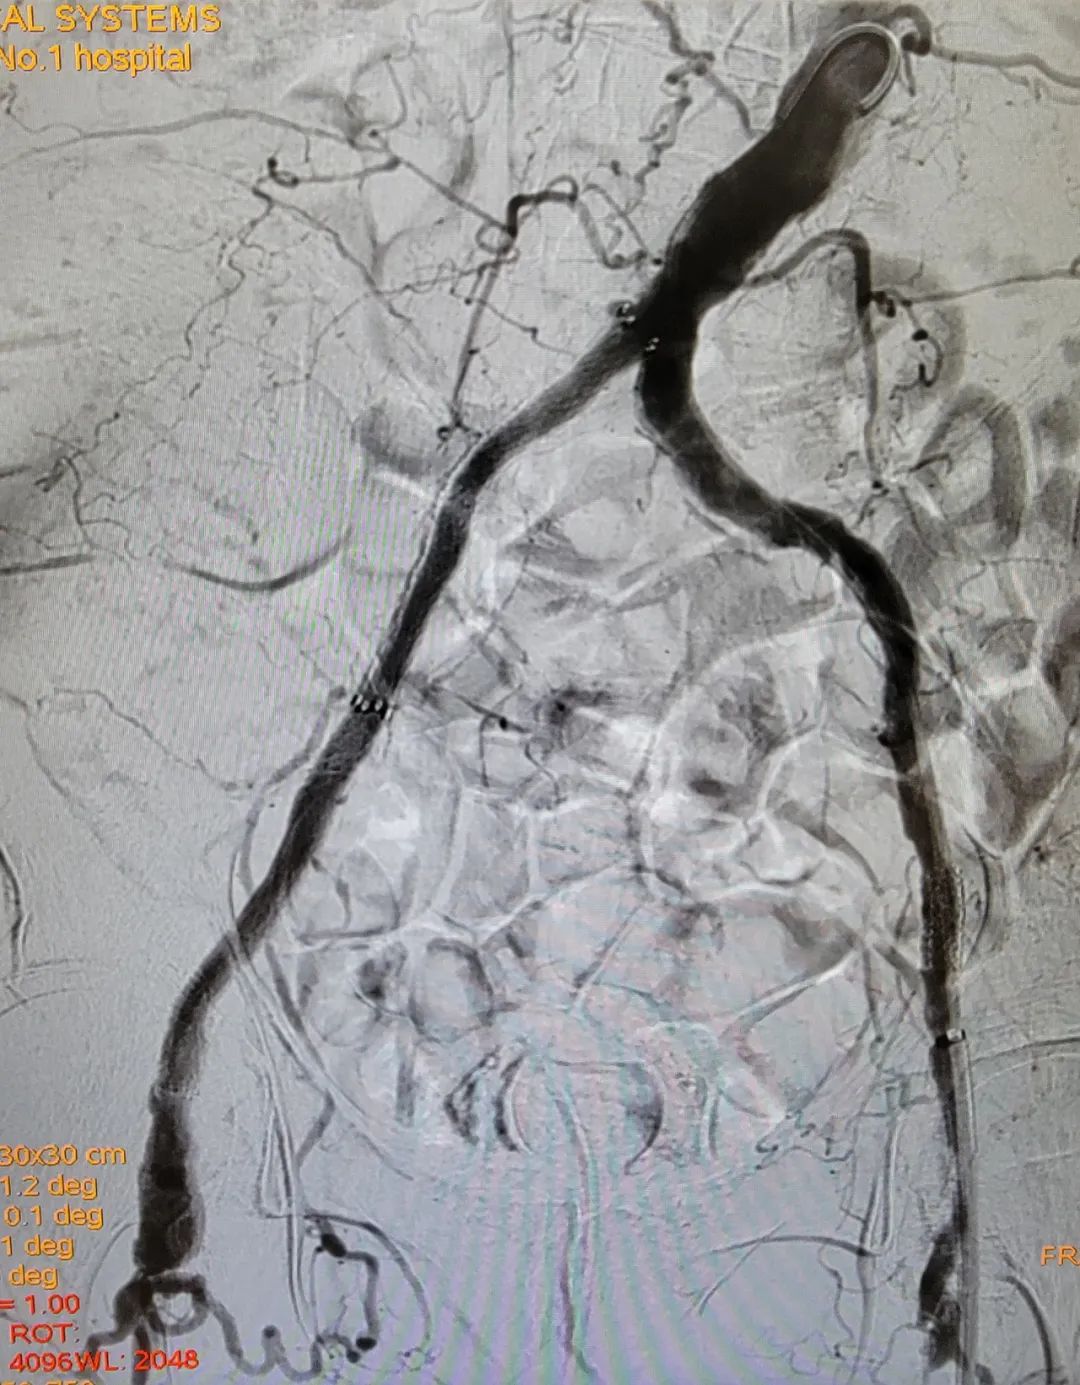

为此,熊小蔚及其团队提出为刘大爷进行分期手术,在镇静、镇痛辅助局麻条件下进行第一期行动脉斑块切除+支架植入的复合手术,重点解决刘大爷静息痛的问题。同时,经过一期手术后的血管代偿机制,刘大爷脚部的溃疡很有可能自愈,这样既满足了刘大爷病情治疗的需求,也最大程度减少了风险的发生。

在经过和刘大爷及其家属的充分沟通后,手术顺利进行,术中既开通了闭塞的双侧髂动脉,同时也保护好了刘大爷原有的侧支血管,最大程度保障了下肢的动脉血流灌注,双足的缺血症状明显改善、坏疽范围得到控制,同时,也没有出现湿性坏疽及感染等情况。经过精心的护理,刘大爷顺利出院了。